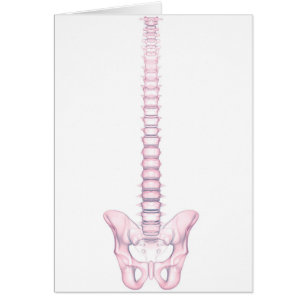

Développement De La Fistule

Prix de vente 5.44 CHF. Prix Initial 6.04 CHF.